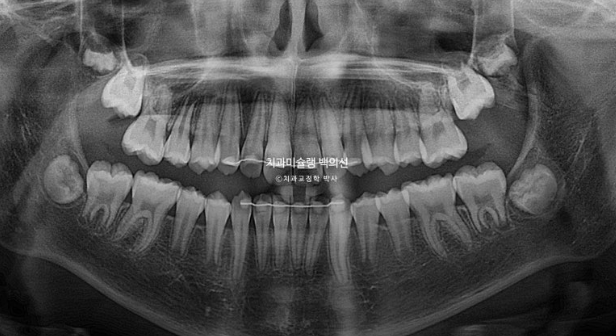

23.06~25.06

치근평행도는 좋으며 치근흡수는 없습니다.